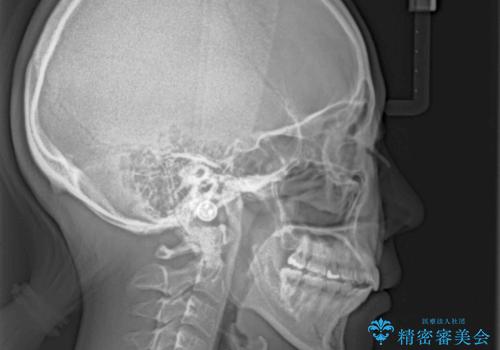

残存乳歯とオープンバイト インビザラインによる矯正治療

- 前歯のデコボコと咬み合わせを気にして来院された患者様です。

左上奥歯には乳歯が残存しており、後続永久歯は舌側に転位していました。

また、舌の突出癖の影響で上下前歯が接触していないオープンバイトとなっており、奥歯に負担のかかる咬み合わせとなっていました。

乳歯を抜歯し、舌側の永久歯を引っ張り出すこととしましたが、希望のインビザラインでは移動量が大きすぎて対応できない可能性があったため、ワイヤー装置にて改善することとしました。

ワイヤー装置にてある程度歯列が改善されたところで、上下をインビザラインにて矯正治療を行うこととしました。

舌のトレーニングをしっかりと行ってくださり、前歯部のオープンバイトは大幅に改善されました。

もう少しでよりタイトに前歯が接触できそうでしたが、患者様がもう十分とのことで治療を終了しました。